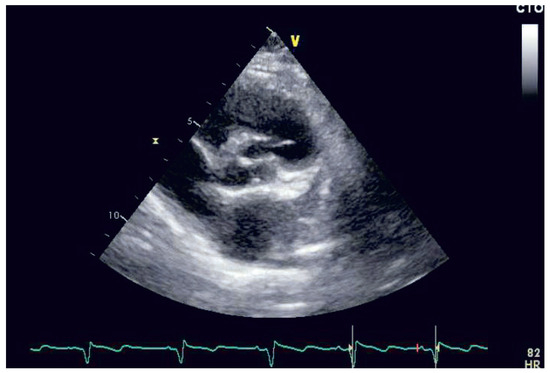

The Weak Heart: Perioperative Management

by Dominique Anne Bettex, Pierre-Guy Chassot and Alain Rudiger

Cardiovasc. Med. 2015, 18(10), 273; https://doi.org/10.4414/cvm.2015.00362 - 21 Oct 2015

Heart failure (HF) is known to be a major risk factor in perioperative care. It should be subdivided into systolic or diastolic dysfunction as well as left or right ventricular failure. The perioperative management of HF patients is complex, consisting of prevention, diagnosis [...] Read more.

Heart failure (HF) is known to be a major risk factor in perioperative care. It should be subdivided into systolic or diastolic dysfunction as well as left or right ventricular failure. The perioperative management of HF patients is complex, consisting of prevention, diagnosis and therapy. The adequacy of the perioperative management determines the late postoperative outcome and will be presented in this review. Full article

Show Figures

Figure 1